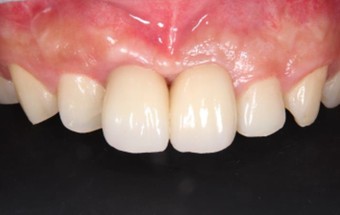

20代 男性

治療前

治療後

治療後- リスク・副作用

- 術後疼痛、歯肉腫脹

- 治療の費用

- 合計¥701,000(税込)

【内訳】

インプラント(1本)¥440,000

その他費用¥261,000

(薬・注射・レントゲン・CT・データ分析・骨造成・サージカルステント・血液検査・仮歯) - 年齢/性別

- 20代/男性

- 患者の具体的な症状

- 1年前に左上12 右上1の根の治療をし、その後放置していたら、左上2が破折した。

左上2インプラント補綴 左上1右上1オールセラミック装着。

歯根破折と虫歯による痛み、審美障害を主訴として来院。 - 検査方法

- コーンビームCT、レントゲン撮影

- 診断結果

- 左上2 歯根破折

- 治療詳細

- 左上抜歯後、インプラント埋入1本

骨造成あり 局所麻酔

インプラント治療後、左上1右上1セラミック修復2本 - 通院回数

- 9回

- 治療期間

- 12か月